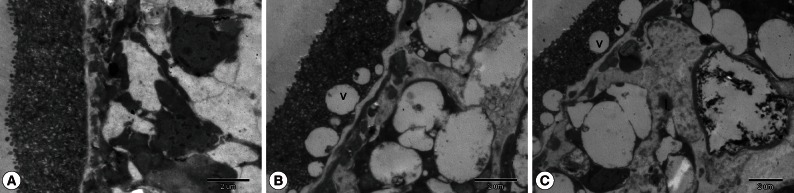

To visualize the structural alterations in protoscolices imposed by SB202190 treatment, parasites were processed for scanning (SEM) and transmission electron microscopy (TEM) after the initiation of treatment with 40 µM SB202190. Control cultures exhibited no ultrastructural alterations in parasite tissue during the whole incubation period (Figs. 2A, 3A). In contrast, morphological and ultrastructural damages were detected in treated protoscolices. At day 3 post-incubation, observations by SEM and TEM of protoscolices incubated with SB202190 revealed the ultrastructural changes. The ultrastructural changes included tegumental alterations (Fig. 2B), rostellar disorganization, loss of hooks, and shedding of microtriches of the scolex region (Fig. 2C). In some protoscolices, loss of morphology was evident (Fig. 2D). Ultrastructural studies by TEM revealed severely affected internal tissues, resulting in loss of its integrity, an increase in the number of lipid droplets, and an increase of vacuoles (Fig. 3B, C).

SB202190 is a pyridinyl imidazole derivative and is known to be a specific inhibitor of p38 MAPK. In line with these studies, we have proved that SB202190 is effective in inactivating in vitro cultured E. granulosus protoscolices. Moreover, the increased effectiveness was induced proportionally with increased concentrations of SB202190. Protoscolices cultured with 80 µM SB202190 were killed considerably faster than protoscolices cultured with 40 µM, 20 µM, and 10 µM SB202190. After 1 day of exposure to 80 µM SB202190, viability was approximately 30%, and it was reduced to 5% after 4 days of incubation. As demonstrated in our experiments, the incubation of drug produced ultrastructural alterations with tegumental alterations, rostellar disorganization, and loss of hooks, and the internal tissue was severely affected. In vitro SB202190 did show some potential as a scolicidal agent for inactivation of the hydatid cyst.

Transmission electron microscopy of E. granulosus protoscolices treated with DMSO (A) or 40 µM SB202190 (B, C) for a period of 3 days. Note the presence of vacuoles (v) and lipid droplets (l).

Fig. 3 Transmission electron microscopy of E. granulosus protoscolices treated with DMSO (A) or 40 µM SB202190 (B, C) for a period of 3 days. Note the presence of vacuoles (v) and lipid droplets (l).